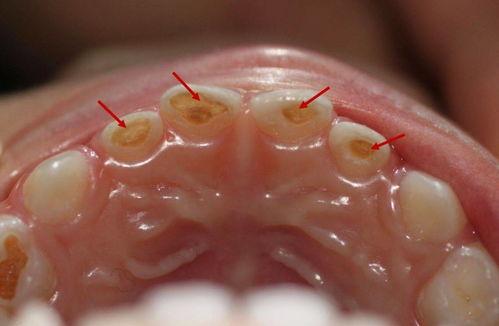

深齲

如果齲齒沒有得到及時(shí)治療,繼續(xù)向深層發(fā)展,侵犯到牙本質(zhì)深層甚至接近牙髓腔時(shí),就稱為深齲。深齲患者在受到刺激時(shí),疼痛會(huì)更加明顯和持久,甚至在沒有刺激的情況下也可能出現(xiàn)自發(fā)性疼痛。齲洞往往較大且深,可能已經(jīng)接近牙髓腔。

深齲:對(duì)冷、熱、酸、甜等刺激敏感,疼痛較明顯且持續(xù)時(shí)間較長(zhǎng)。刺激去除后,疼痛仍可能持續(xù)一段時(shí)間。

深齲:齲洞較深,可達(dá)牙本質(zhì)深層,探針探查時(shí)感覺較軟,有時(shí)可以探到接近牙髓腔。

深齲:牙髓可能會(huì)有輕度的炎癥反應(yīng),牙髓活力測(cè)試可能會(huì)出現(xiàn)短暫的敏感。

深齲:X射線片上可以看到齲洞較深,接近牙髓腔,有時(shí)可能會(huì)伴有牙髓腔的輕度縮小。